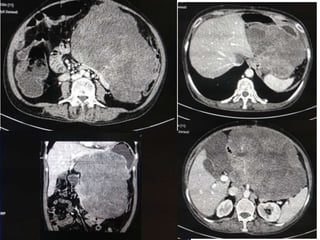

 55 yr old female patient

 Presented with complaints of lump abdomen and vague

abdominal discomfort

 Bowel habits normal with no other gastrointestinal complaints

CASE 2

CASE2

DIFFERENTIALS

Diagnosis Points in favour Points against

Retroperitoneal

sarcomas

• Leiomyosarcoma

/Undifferentiated

Liposarcoma

• MFH

Age and clinical

presentation

Imaging features

(Large ill defined

heterogeneously

enhancing lesion

with areas of

necrosis)

No fat density/

calcification

No calcification

GIST Age

Biopsy:

 Poorly differentiated Leiomyosarcoma